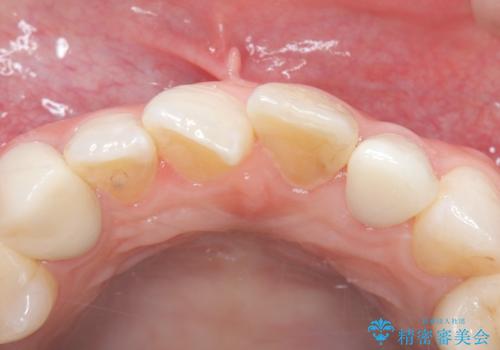

外れ欠けている土台をまずやり替えた後、根管治療後の緊密な封鎖を目的としオールセラミッククラウンをセットしました。

・仮歯:10,000円(税抜き)

・ファイバ-コア(土台):20,000円(税抜き)

・オールセラミッククラウン(スタンダード):110,000円(税抜き)